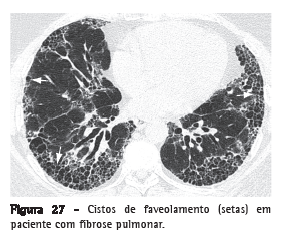

Faveolamento (favo de mel)Cistos pulmonares criados pela destruição de espaços aéreos distais, por fibrose do parênquima pulmonar, com desarranjo da arquitetura de ácinos e bronquíolos. Os cistos de faveolamento são revestidos por epitélio bronquiolar metaplásico e representam o estágio terminal de várias doenças pulmonares.(1,48) Na TCAR, caracteriza-se por múltiplos cistos, em geral de localização subpleural, com diâmetros semelhantes (tipicamente de 0,3-1 cm), agrupados em camadas e compartilhando

paredes bem definidas de 1-3 mm de espessura (Figura 27).(49)

Representa um marcador tomográfico de fibrose pulmonar. As causas principais incluem fibrose pulmonar idiopática, colagenoses, pneumonite por hipersensibilidade crônica, reações pulmonares medicamentosas e asbestose.(28) Deve ser diferenciado de enfisema parasseptal e de bronquiolectasia de tração.